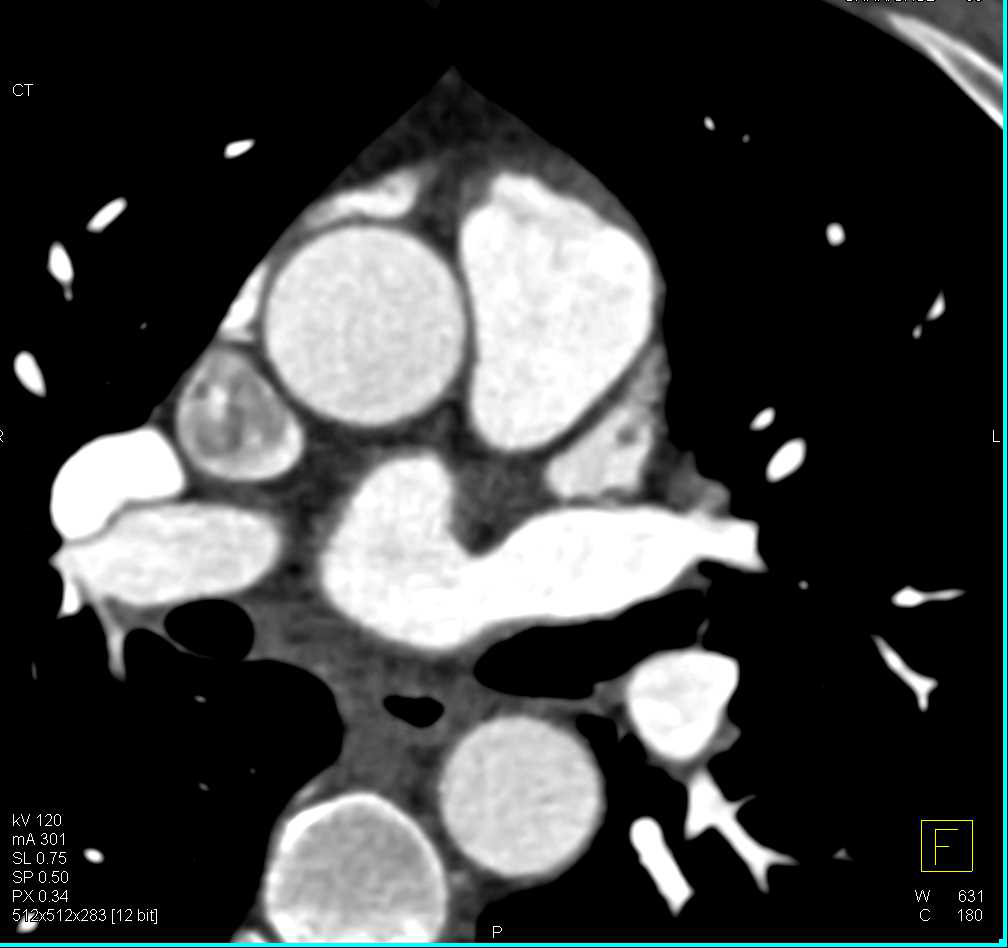

Aortic Root Repair and Type A Dissection